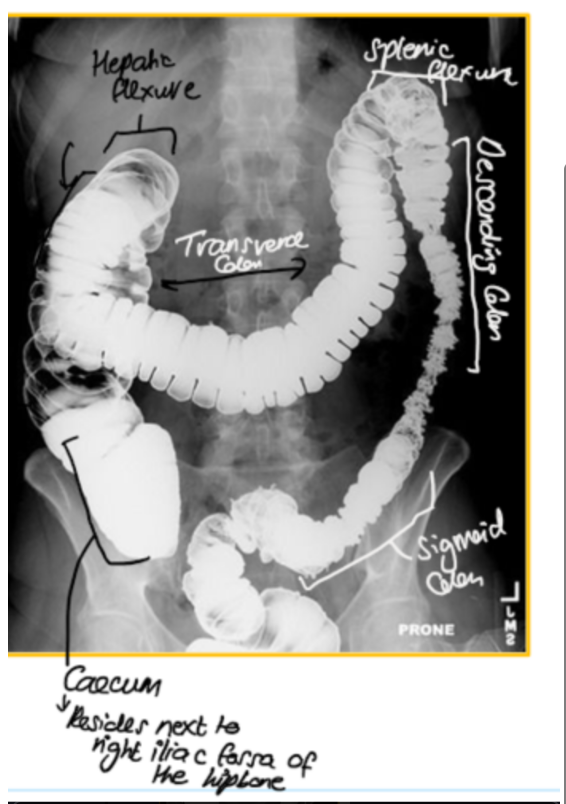

Q

Label the parts of the colon/ large intestine on the X-ray

A

where does cecum reside?

next to right illiac fossa, before becoming the ascending colon